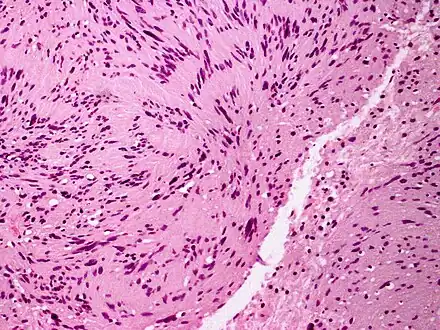

Palisaded encapsulated neuroma

| Micrograph of a palisaded encapsulated neuroma | |

Palisaded encapsulated neuroma (PEN) is a rare, benign cutaneous condition characterized by small, firm, non-pigmented nodules or papules.[1][2] They typically occur as a solitary (single) lesion near the mucocutaneous junction of the skin of the face, although they can occur elsewhere on the body.[3]

As mentioned previously, PEN is a benign, firm, flesh-coloured lesion that typically occurs in dermis of the skin of the face. The lesions are typically between 2–6mm and are slow-growing.[3][4]

PEN is diagnosed by clinical recognition of the lesion and on subsequent histologic examination. Typically, the lesions are suspected to be schwannomas or neurofibromas clinically with PEN being an incidental finding on histology.[3]

PEN is typically diagnosed in patients between the ages of 40 and 60 years and occurs more frequently in females than males. The diagnosis of PEN may be difficult, even with confirmatory histology, due to its histological similarities with schwannomas and neurofibromas. It is imperative that the correct diagnosis is made the misdiagnosis of a neurofibroma may lead to unnecessary further investigation into associated systemic syndromes such as neurofibromatosis type 1 or multiple endocrine neoplasia syndrome.[3][4]